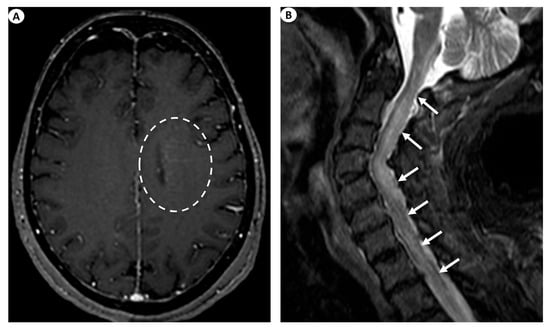

The most commonly encountered imaging manifestations include T2 signal abnormalities in the periventricular white matter. This finding’s presence has been documented in as low as 11.8% [9] and up to 75% [1] of patients. Nonetheless, besides the periventricular white matter, T2 signal abnormalities may also be recognized, affecting various different regions such as the basal ganglia, the thalami, the cortex, the brainstem, the cerebellum, and even the hippocampus. Specifically, in a 2021 study by Xiao et al. [9], basal ganglia and thalamic lesions were displayed in up to 41.2% of the patients, cortical lesions were displayed in 29.4% of the patients, while lesions were also depicted in the brainstem (23.5%), the cerebellum (5.9%), and the hippocampus (5.9%). Similarly, in a recent relevant study by Ke et al. (2024) [26], the evaluation of brain MRI examinations in 33 patients with GFAP astrocytopathy demonstrated T2/FLAIR abnormal hyperintensities in the vast majority of the cases studied (90.9%), most usually with a juxtacortical (54.5%) or a periventricular (48.5%) white matter localization, followed by lesions in the basal ganglia (45.5%), the brainstem (33.3%), the thalami (27.3%), and the cerebellum (6.1%). However, T2 periventricular white matter hyperintensities are a largely unspecific imaging finding.

On this note, a remarkable imaging finding considered a hallmark of GFAP astrocytopathy, which can be detected after intravenous gadolinium contrast agent injection, is a linear perivascular pattern of enhancement, which is usually located in the periventricular white matter in GFAP-enriched regions and extends outwards in a radial pattern [27,28]. This significant finding has been documented in as low as 23.5% [9] to up to 53% [2] of patients. Other manifestations of cerebral enhancement patterns may include leptomeningeal enhancement, encountered in as low as 33% [1] to up to 45.5% of patients [18], periependymal enhancement [28], as well as punctate or serpentine enhancement [4].

Likewise, GFAP astrocytopathy may also affect the spinal cord, producing signal abnormalities and abnormal enhancement [28]. Specifically, patients with clinical suspicion of myelitis may demonstrate extensive long-segment myelitis, illustrated as T2 signal hyperintensity with a caudocranial extension of more than three vertebral bodies with or without concomitant contrast enhancement with a linear, punctate, or patchy pattern [27]. To further analyze, in a study by Fang et al., a longitudinally extensive increase in the T2 signal was detected in up to 71% of patients with myelopathy, although up to 29% had a normal spine MRI study [1]. In the study by Xiao et al. on 15 patients undergoing spine MRI, 53.3% displayed the typical finding of longitudinal myelitic lesions, 26.7% had short myelitic lesions, and up to 20% had a normal spine MRI study. Central canal or leptomeningeal contrast enhancement was seen in 66.7% and 13.3% of patients, respectively [9]. In the study by Ke et al. (2024), an abnormal T2 hyperintense signal in the spinal cord was displayed in 19/27 cases undergoing spine MRI (70.4%), more commonly affecting long segments (55.6%) and the thoracic spinal cord (25.9%). Moreover, in the cases undergoing intravenous gadolinium injection, abnormal spinal cord enhancement was seen in 59.1%, most frequently exhibiting a leptomeningeal pattern of enhancement (54.5%), followed by enhancement in the central spinal canal (36.4%) [26].

Figure 3.

(A) Axial T1-weighted contrast-enhanced images following intravenous gadolinium injection demonstrate subtle periventricular linear contrast enhancement on the left cerebral hemisphere extending outwards in a radial pattern in a patient with GFAP astrocytopathy (dashed oval). (B) Sagittal fat-saturated T2-weighted images display abnormal signal hyperintensity extending craniocaudally from the cervicomedullary junction throughout the whole cervical spinal cord to the thoracic spinal cord (more than three vertebral levels affected), findings indicative of longitudinally extensive myelitis (arrows) in a female patient with GFAP astrocytopathy.